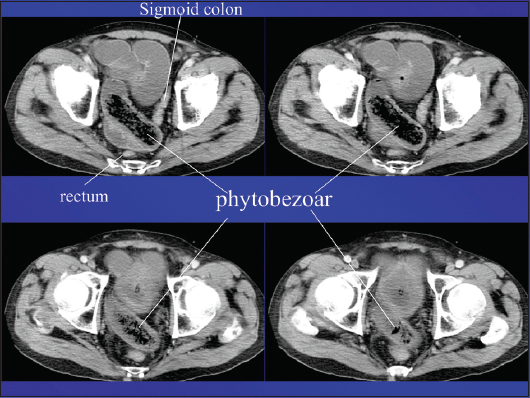

Radiological imaging also plays a crucial role in the diagnostic approach. Plain X-rays may show air-fluid levels that suggest intestinal obstruction, while barium studies may contribute to the differential diagnosis among intestinal diverticuli, adenomas, malignancies and bezoars (Fig. 1). Unfortunately, these studies are insufficiently accurate and are inappropriate for detailed emergency investigation, or for the preoperative assessment of intestinal perforation or complete obstruction [50]. Undoubtedly, contrast-enhanced computed tomography (CT) scanning is the radiological method of choice, showing high sensitivity (up to 90%) and specificity (up to 60%). Phytobezoars, the most common bezoars, are visualized as round or ovoid masses with air-bubbles and a mottled appearance [51] (Fig. 2). Interestingly, they may appear similar to small bowel feces; the latter are discovered in about 8% of cases with ileus. It should be noted that, on radiological imaging, feces tend to appear in a longer segment and are associated with sharp-margin dilatation compared to bezoars, which tend to slide back and forth intraluminally [52,53].

Figure 2 Contrast-enhanced computed tomography showing a phytobezoar in ileal loops causing intestinal obstruction (characteristic mottled appearance)